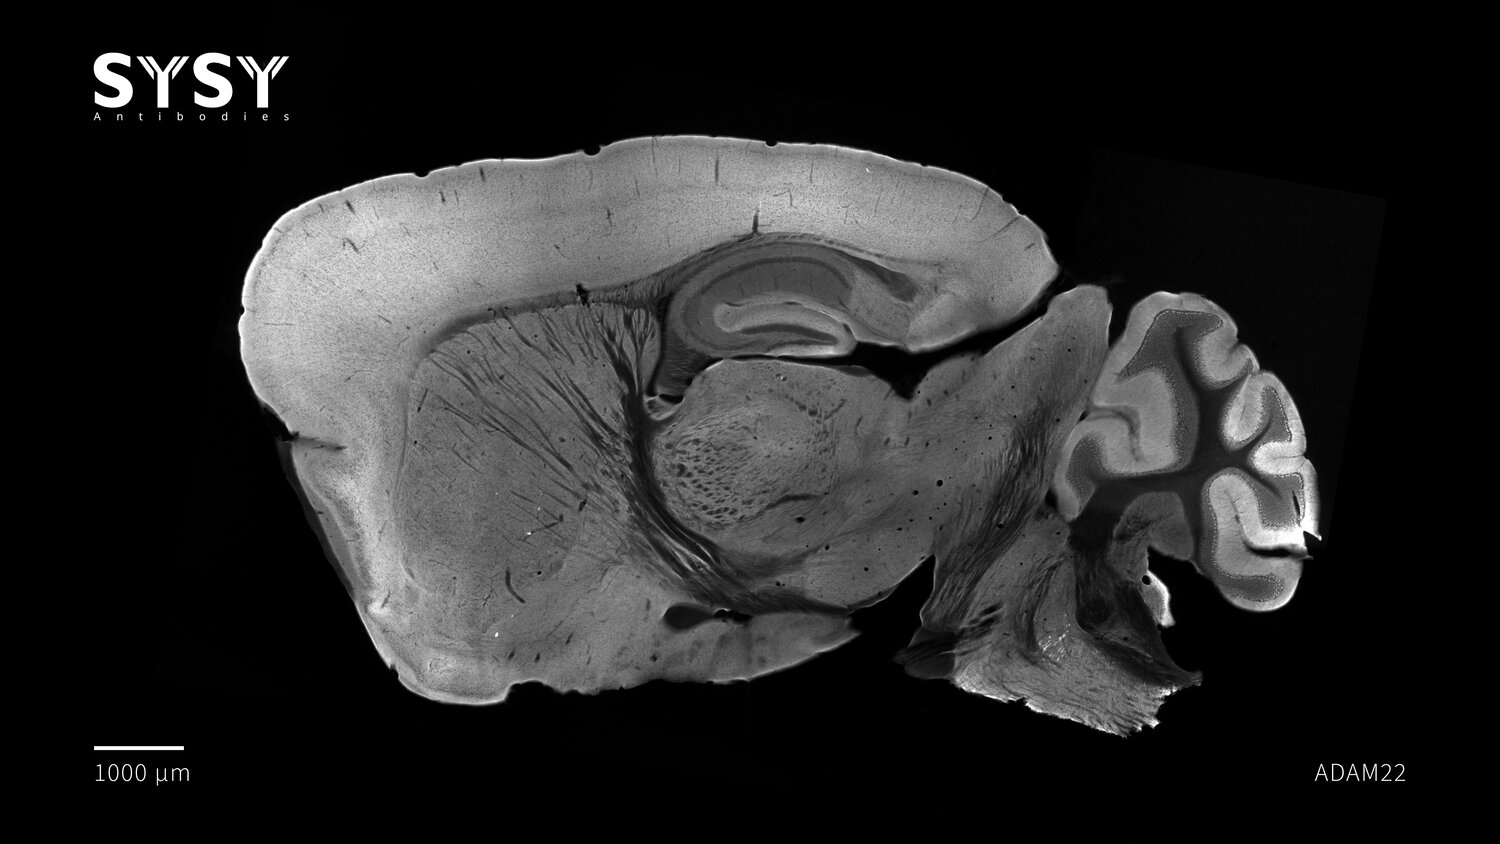

ADAM22

Indirect immunostaining of a formaldehyde fixed sagittal mouse brain section with guinea pig anti-ADAM22 antibody (cat. no. 317 005, dilution 1 : 500).